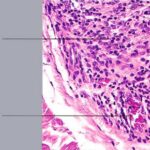

The diagnostic pathologic feature is peribulbar lymphocytic inflammation (“swarm of bees”) affecting anagen follicles or follicles in early catagen. The inflammatory assault on anagen follicles induces a premature conversion to catagen . Consequently, the number of catagen and telogen follicles found may be marked, approaching 100% . Follicles may enter a persistent phase of telogen in which the hair shaft has already been shed, manifested by the telogen germinal unit .As follicles enter catagen, the lymphocytic infiltrate may persist around the epithelial remnant of the receding follicle and also within and surrounding the collapsed follicular sheaths. Telogen hairs show little to no perifollicular inflammation.

Lymphocytes may also be seen sparsely infiltrating the matrix epithelium of anagen follicles, inducing damage to the matrical cells that includes intra- and intercellular edema, cellular necrosis, and microvesicle formation. One of the earliest findings was shown to be a loss of structural integrity of bulbar keratinocytes in the central part of the supramatrical bulb and shrinkage of hair bulbs toward a club shape . As a result of injury to bulbar melanocytes and keratinocytes, pigment casts, which are clumps of melanin pigment, may be found within the dermal papilla, the sheath of miniaturizing or regressing follicles, or the follicular epithelium . Pigment casts